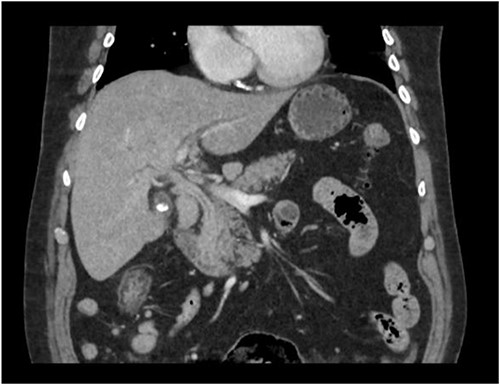

A man in his 70s presented to the emergency department with painless obstructive jaundice with dark urine and pale stools. The patient denied having any fever, nausea, vomiting, or weight loss. Liver function test progressively worsened during the admission peaking at a bilirubin of 287 umol/L (normal 2–20), alkaline phosphatase 694 U/L (normal 30–110), and alanine aminotransferase 160 U/L (normal < 40). Initial assessment on computed tomography and ultrasound raised concerns for primary pancreatic head neoplasm or cholangiocarcinoma (Fig. 1). He subsequently underwent magnetic resonance cholangiopancreatography (MRCP), which showed involvement of the entire common bile duct with no definite stricture or dilatation and no discrete pancreatic head mass (Fig. 2). Positron emission tomography showed abnormal uptake in the intrahepatic and extrahepatic bile ducts, focal uptake in the tail of the pancreas, and lymph nodes in the porta hepatis, retroperitoneum, and right iliac fossa (Fig. 3). Tumour markers revealed a carbohydrate antigen 19-9 (CA19-9) of 3286 kU/L (normal < 34).

CT scan showing thickening and enhancement of the entire extrahepatic common bile duct with intrahepatic duct dilatation.